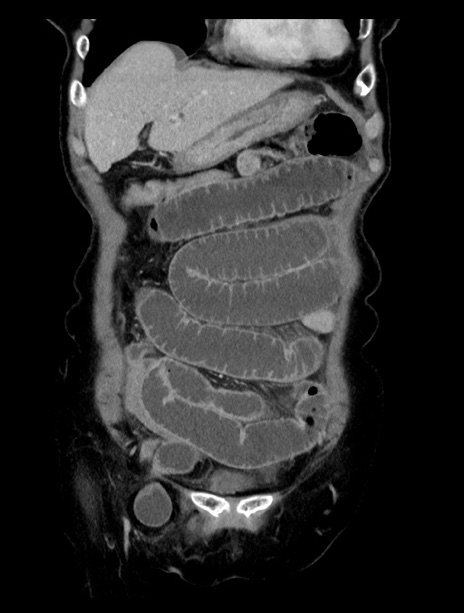

症例23(冠状断像)

【症例】70歳代女性

【主訴】下腹部痛・嘔吐

【現病歴】2日前より腹痛あり。昨日嘔吐あり。症状改善しないため来院。

【既往歴】胃GISTに対して胃部分切除後。

【身体所見】BT 37.1℃、BP 128/77mmHg、腹部:平坦・軟、下腹部に圧痛あり。

【データ】WBC 10200、CRP 0.31